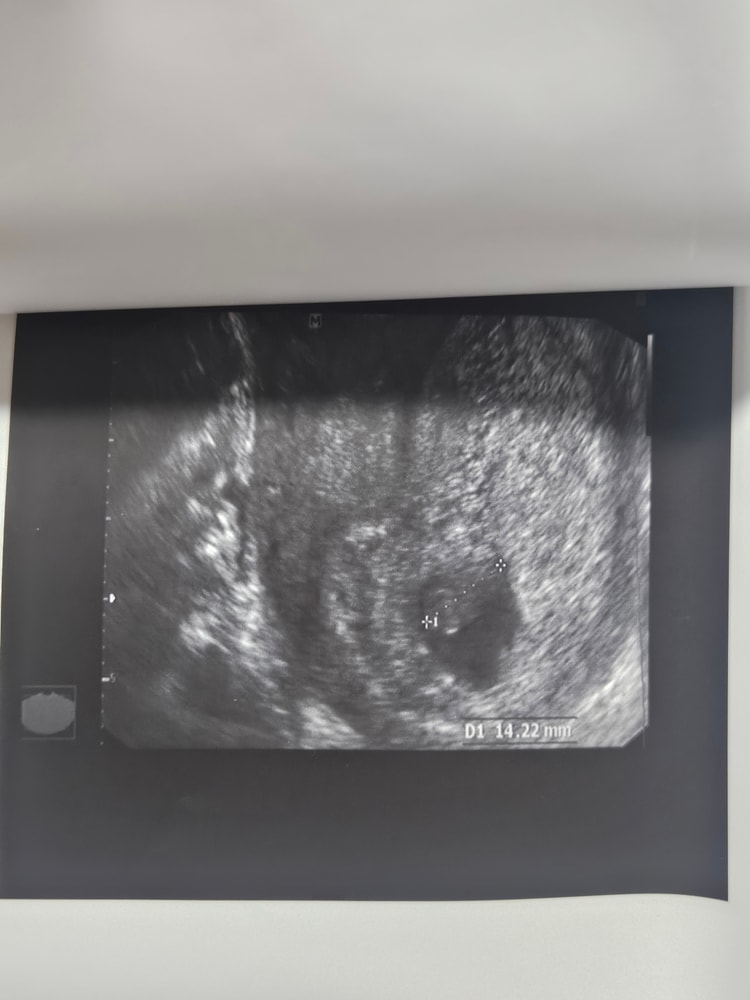

Беременность 9 недель. Сказали сделать контрольное УЗИ перед 1 скр. Сходила в платную клинику 11.04, эмбрион видно плохо( по словам УЗИ-специалиста рассасывается), СБ нет, поставили в заключении : "ЗБ 7.4 недель.Пузырный занос с множеством кист" . p.s: Ходила я на УЗИ 22.03 было СБ и эмбрион было видно. (За 2 недели-то меня что-то могло начать беспокоить).

12.04 я решила ещё в другую платную клинику сходить, эмбрион нашли с трудом(все так же не четко визуализируется), КТР 16мм, СБ +, прогрессирующая? ,тонус матки

прикреплю снимки узи за 12.04